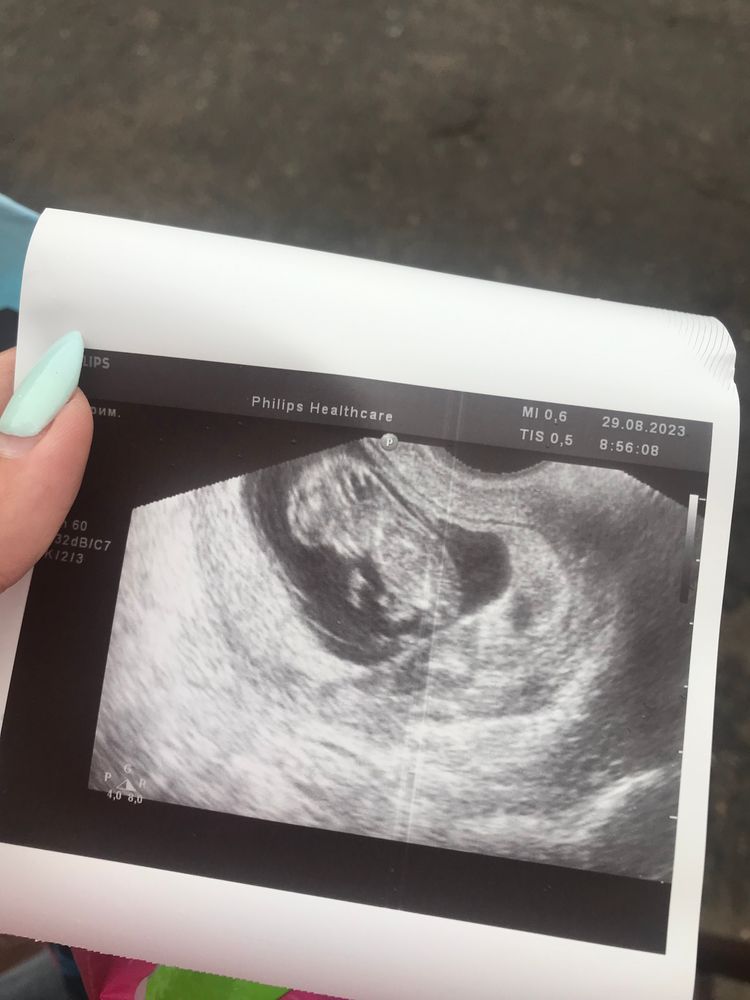

У меня глюк или там по мимо малыша ещё 3 круглых ? Хотя на УЗИ сказала УЗИстка что их нет и они рассосались я не сразу посмотрела когда вышла тогда увидела думала уже крыша едет от многоплодной беременности которой оказывается нету🤣🤣🤣

Какое ужасное узи…яичник еще виден сбоку что ли?

Екатерина, не знаю что там 😂 я пошла посмотреть гематому ну и остальных а тут что то непонятное

Екатерина, я с 3 ребенком ходила к ней вот думаю мб дело в аппарате муж сказал что он дешёвый китайский поэтому и результат такой

Екатерина, у нас у половина б/у не очень дорогие и новые не хотят брать а покупают хлам всякий есть Samsung мало где есть хорошее УЗИ